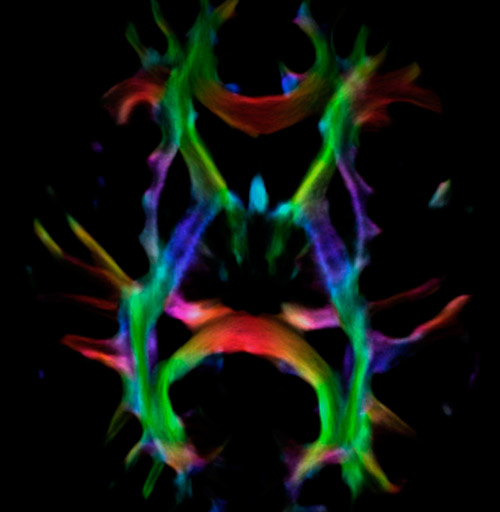

Fiber tractography of the corticospinal tract with seed region of the posterior limb of the internal capsule. Different processing based on the same data.

All images were created from the same acquisition in a child using Ingenia 3.0T CX and 32-channel dS Head coil. Diffusion data was acquired at b-values 0, 500, 1000, 2000, 3000. The use of high b-values (3000 s/mm2) effectively suppresses extra-axonal water signal and provides high angular resolution.

Fiber orientation density

CSD of multishell DWI results in the white matter FOD at each voxel. Unlike the conventional diffusion tensor model, this approach enables accurate modeling of multiple fiber populations within a single voxel.

Crossings of the corpus callosum, corticospinal tracts, and the superior longitudinal fasciculus are shown.

Crossing fibers of the corpus callosum bordered by the superior longitudinal fasciculus as well as within in the pons.

Fiber tracking based on CSD analysis of multishell DWI data and probabilistic tractography.

Fiber tracking from the left and right hippocampi to the fornix.

Fiber tracking from the left and right hippocampi to the fornix (green), and the corticospinal track based on a seed region of the posterior limb of the internal capsule.

DEC TDI

Super-resolution directionally encoded color track-density imaging overlaid on T1-weighted structural MRI.

Super-resolution directionally encoded color track-density imaging